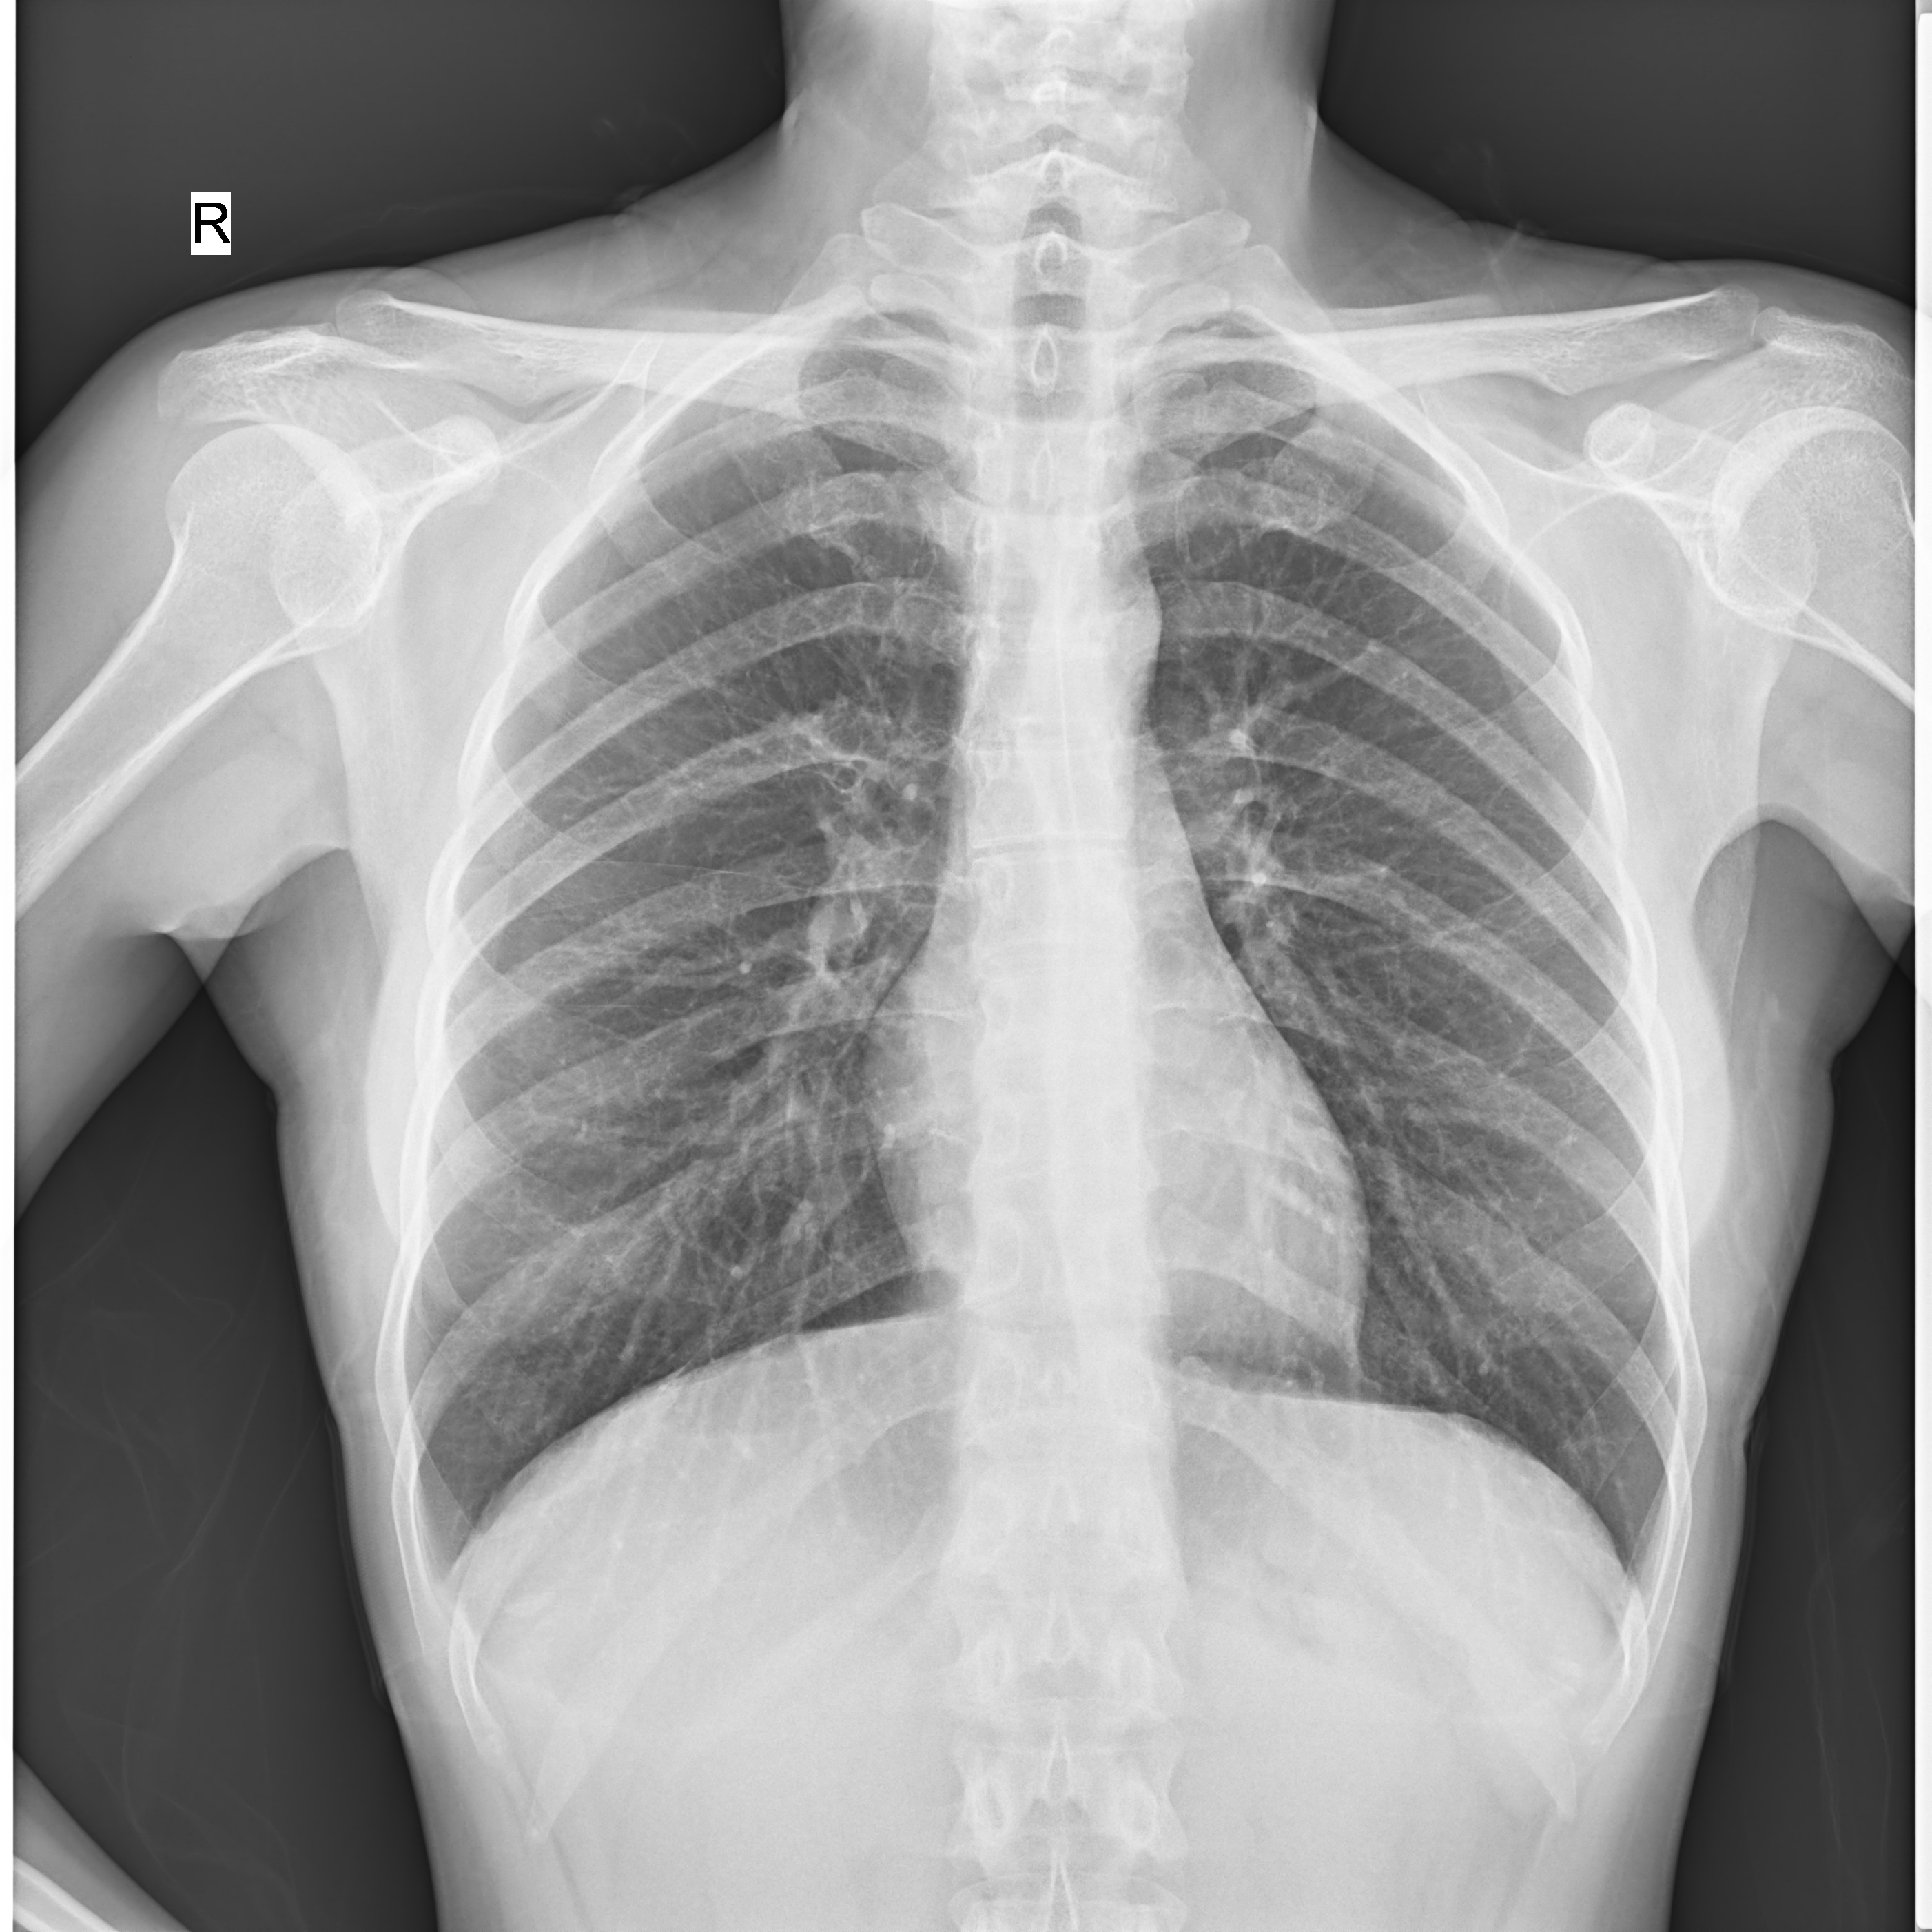

高千伏攝影